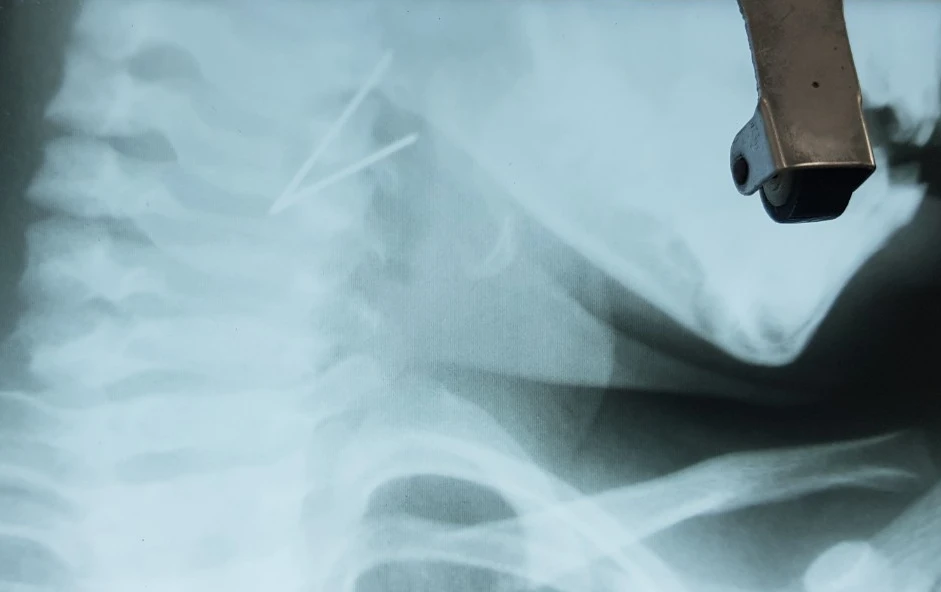

Ảnh X-quang đoạn kim loại cài vào thành họng bé gái. Ảnh: BVCC

Kết quả chụp X-quang cổ cho thấy hình ảnh vật cản quang hình chữ V ở hạ họng. Qua hội chẩn, bệnh nhi được chỉ định nội soi lấy dị vật cấp cứu.

Ê kíp nội sôi đã lấy ra đoạn kim loại dài 7 cm hình chữ V gập góc, một đầu cài vào thành bên họng trái, đỉnh chữ V chặn ngay xoang lê bên trái.